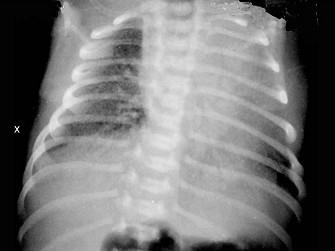

问题 6个月婴儿,发热、咳嗽4天,喘憋2天。体检:体温38.5℃,呼吸75次/min,心率160次/min,口周发绀,呼气延长,伴呼气时呻吟,双肺满布喘鸣音,可闻及少许中小水泡音,肝右肋下2.5cm,质软。血白细胞9×10/L,胸片示双肺透明度增加,双肺纹理增强,见图。应考虑为 ( )

选项 A、支气管肺炎合并心力衰竭 B、腺病毒性肺炎 C、哮喘性支气管炎 D、急性毛细支气管炎 E、急性支气管炎

答案 D